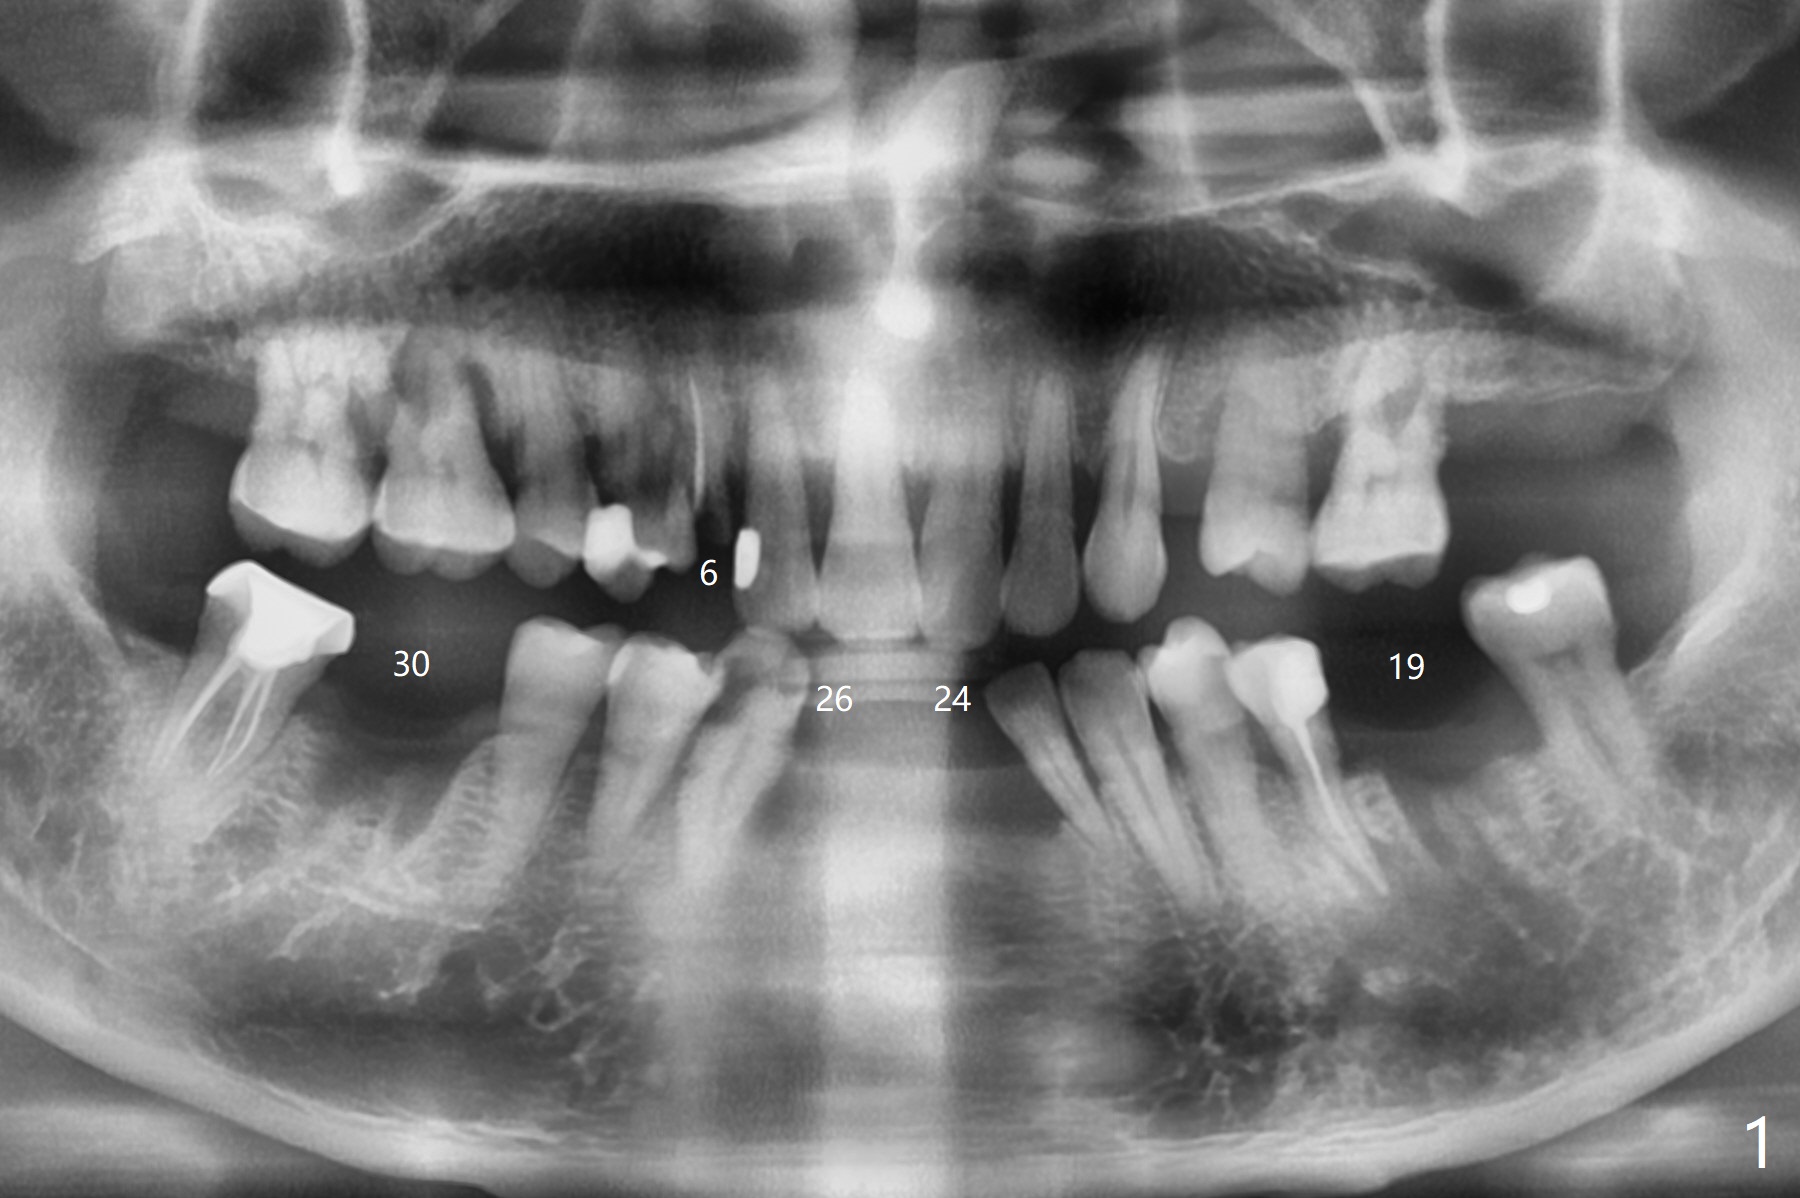

A 51-year-old man with chronic periodontitis requests implants at 19, 24-26 and 30 nearly 2 months post extraction without bone graft (Fig.1). He is willing to quit smoking by using electronic smoke. After SRP, the tooth #6 with supragingival fracture will be saved by post and crown. The mesiodistal space seems to be too narrow for implant (Fig.2). 1-piece implants will be placed at #24 and 26 for FPD (Fig.3,4). Implant placement at #19 and 30 will involve incision, socket redebridement, guide, bone graft (sticky bone), PRF membranes as a barrier and sutures (Fig.5,6).